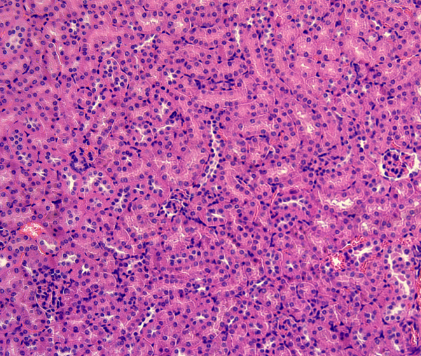

HE染色

苏木精 — 伊红染色法 ( hematoxylin-eosin staining ) ,简称HE染色法 ,石蜡切片技术里常用的染色法之一